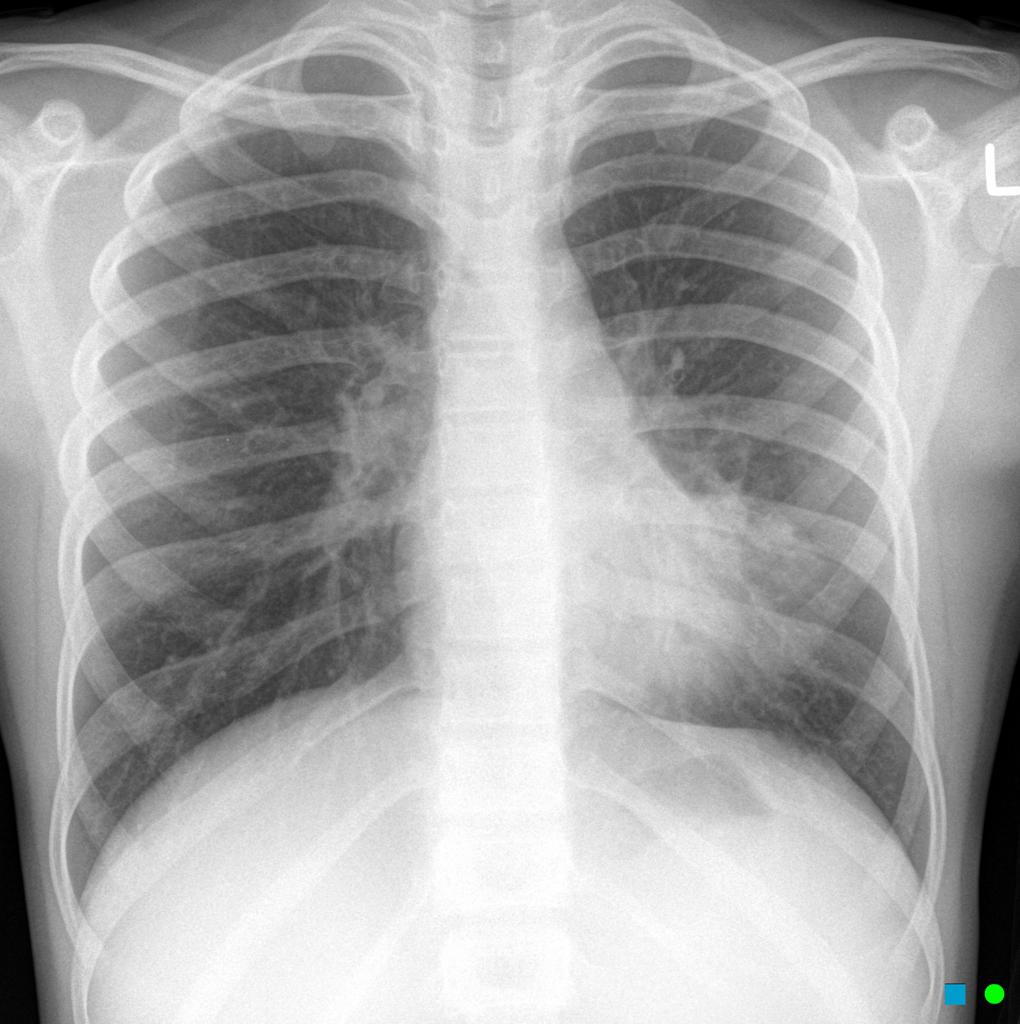

Example 4

Diagnosis

Left Lung Lobar Pneumonia